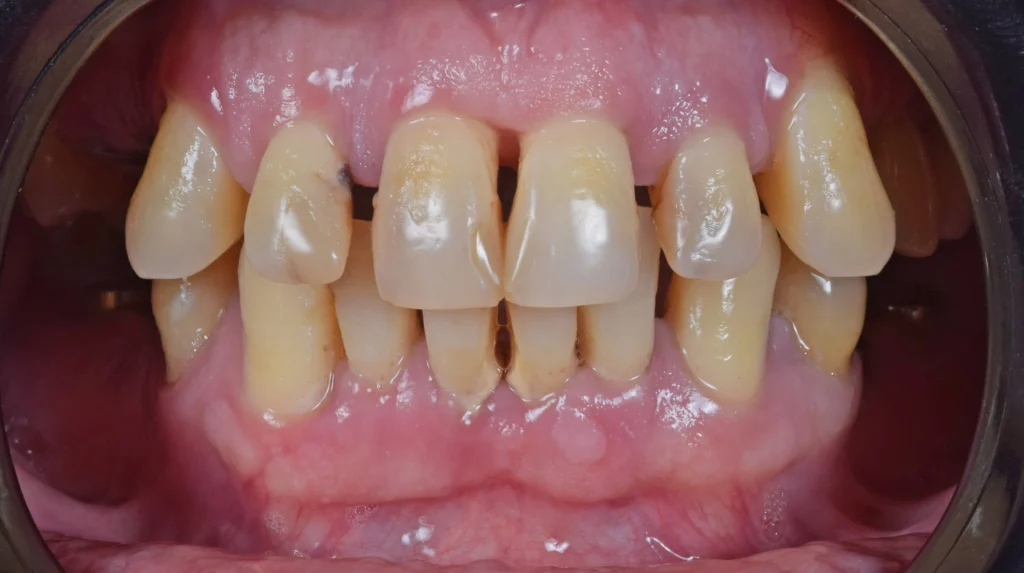

This patient came to our clinic with severe periodontitis and an extreme fear of dental procedures, a combination that had significantly impacted both his oral health and quality of life. Years of discomfort, uncertainty, and anxiety made even the thought of treatment overwhelming.

After a thorough clinical examination and detailed 3D imaging, we developed a carefully structured treatment plan that combined dental implants with the preservation of his natural teeth wherever possible. Our goal was not only to restore function and aesthetics, but also to ensure a comfortable and stress-free experience for the patient.